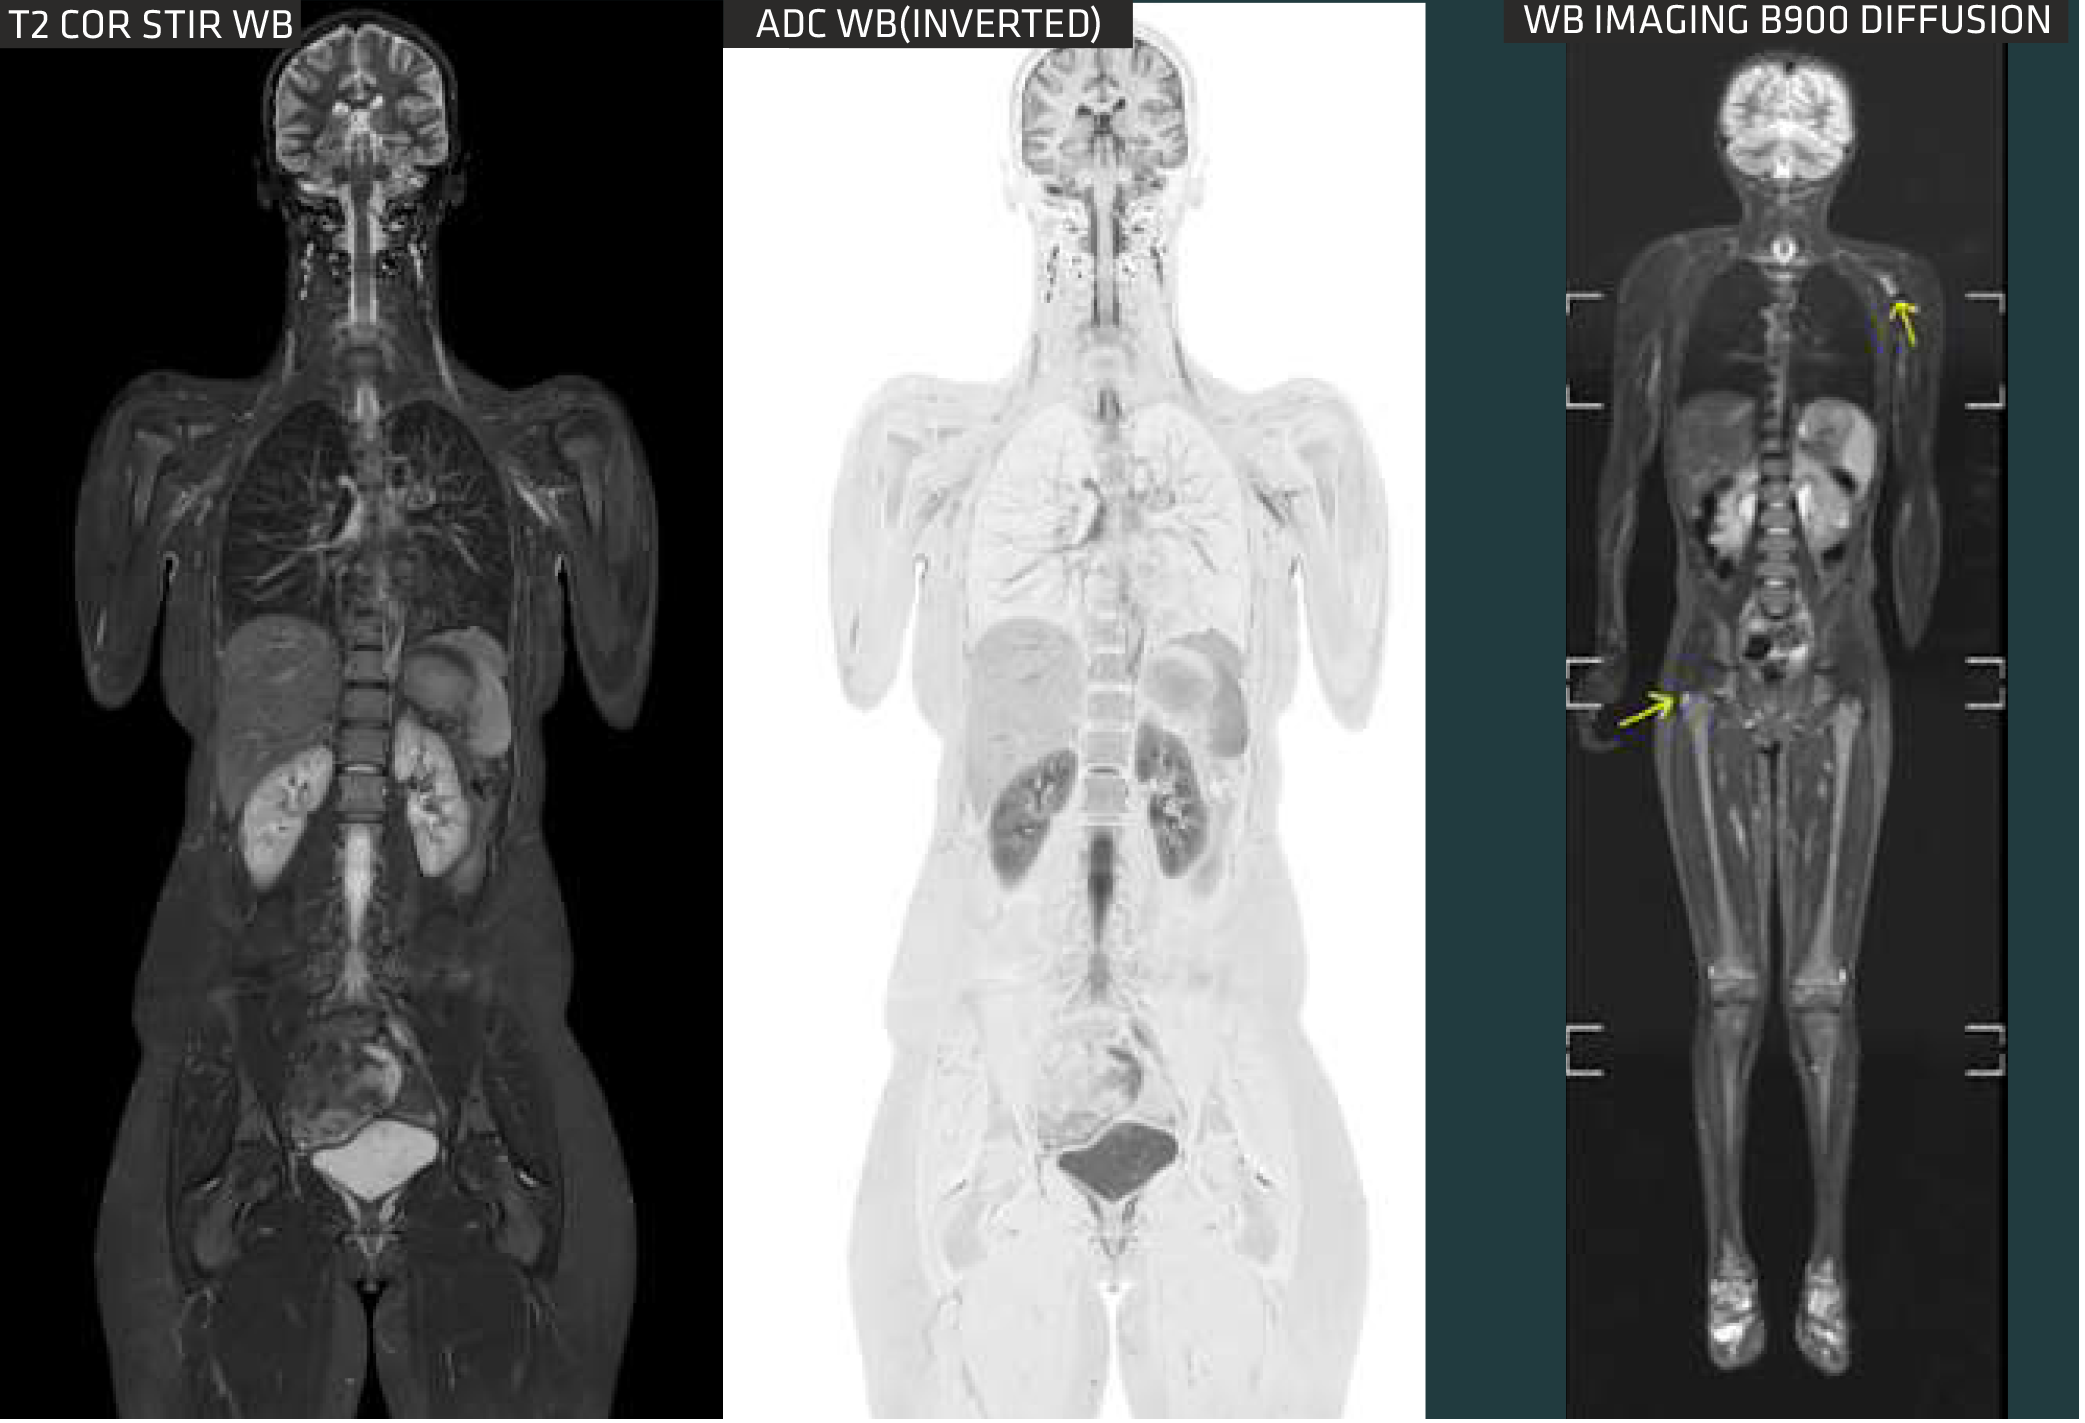

MUSIC (Multi-Segment Imaging Combination) improves MR imaging with flexibility, precision, and speed. It utilizes an array of 66x16 RF channels that run simultaneously in one scan and FOV, hence enabling faster scans. You are required to choose the examination you want, without the need for coil replacement, which improves workflow and increases productivity. With MUSIC, repositioning patients for multiple exams is no longer necessary. Leveraging MUSIC's heightened precision allows us to image small lesions in a whole-body scan

Precision With excellent and pinpointed precision, MUSIC provides excellent images quality from small lesions of the whole body